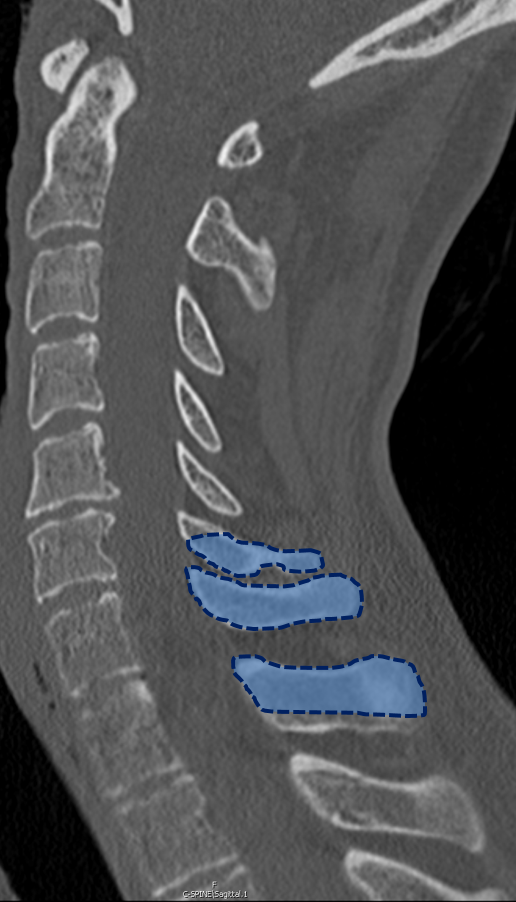

(PDF) C7 extension crosswise osteotomy a novel osteotomy for How To Measure Chest Expansion In Ankylosing Spondylitis This study aims to demonstrate chest expansion and lumbar mobility using modified schober measurement values in healthy male and. Visit us at www.bjchealth.com.auwant to try live virtual. Measuring chest expansion with a tape measure specific for ankylosing spondylitis. The first thing we have to do is to find the the fourth intercostal space, and the way to do that is. How To Measure Chest Expansion In Ankylosing Spondylitis.